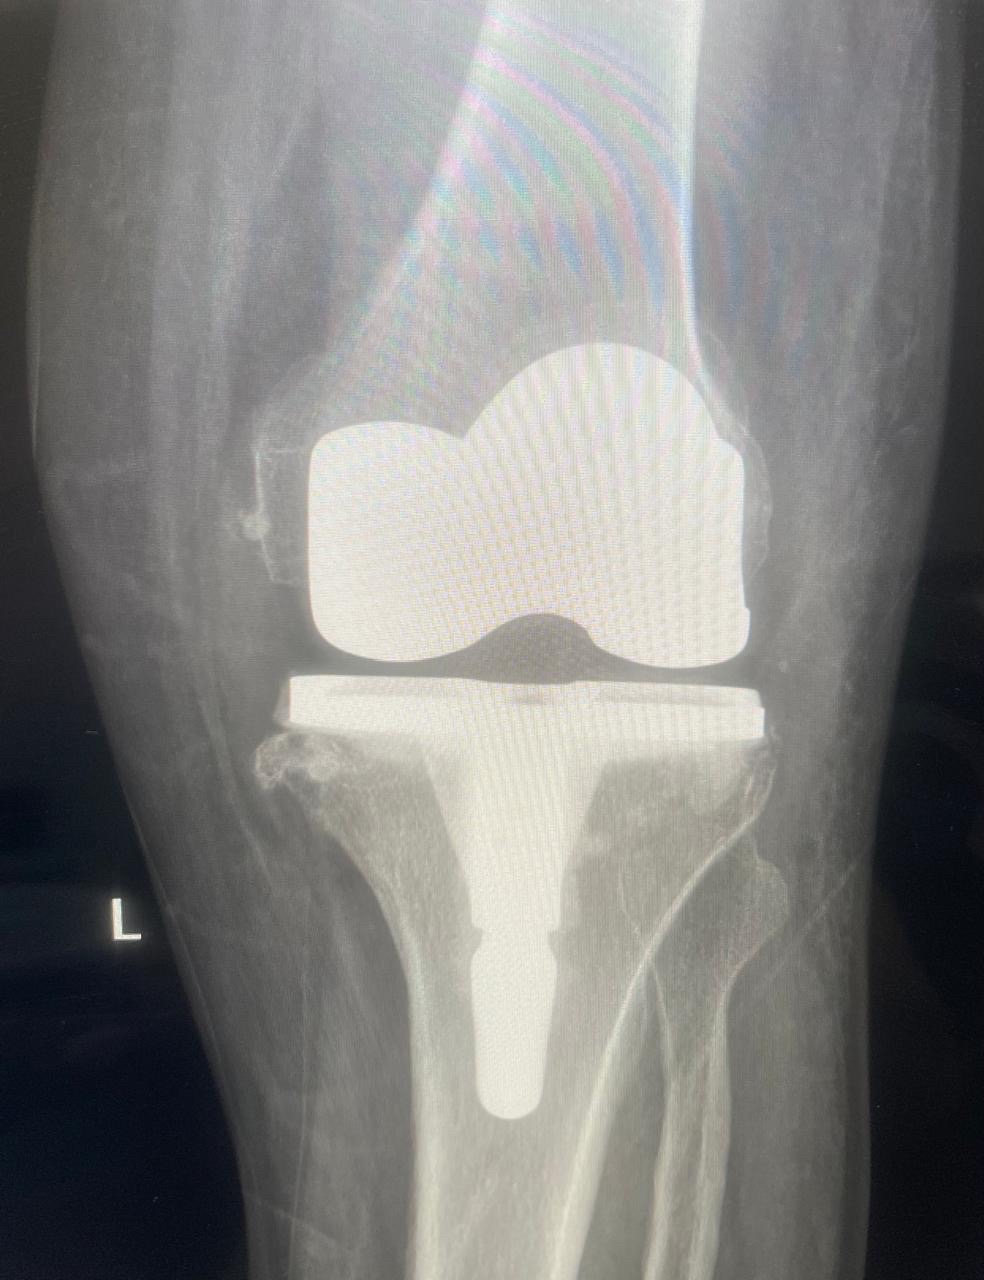

أعلن مستشفى القطيف المركزي إطلاق وحدة تخصصية لتبديل وترميم المفاصل، متوجاً انطلاقتها بإجراء 30 عملية جراحية ناجحة للركبة، لتعزيز كفاءة الرعاية الطبية وتطوير الخدمات وفق أحدث المعايير العالمية المعتمدة.

وأوضح المستشفى التابع لتجمع الشرقية الصحي، أن الوحدة الجديدة انضمت رسمياً للوحدات التخصصية بقسم العظام، مبيناً أن نجاح العمليات الثلاثين يعكس جاهزية الكوادر الطبية وتوفر التقنيات المتقدمة.

وبيّنت الجهات الطبية أن الوحدة تقدم منظومة رعاية متكاملة، تبدأ بتقييم وتشخيص دقيق لحالات تآكل المفاصل والإصابات المزمنة، وصولاً للتدخلات الجراحية المبتكرة.